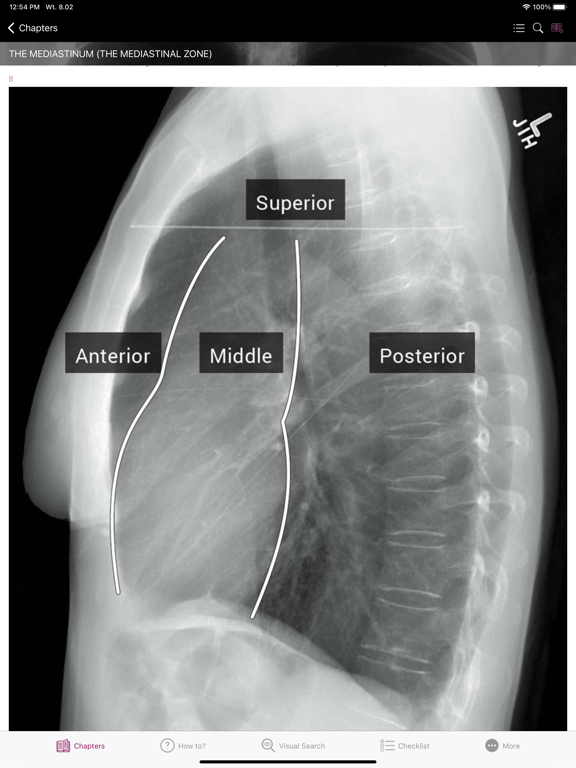

Section II* introduces the concept of radiological zones to give you a starting point in the understanding of the radiological anatomy of the chest. The next chapters review in detail the radiological anatomy of specific anatomical structures, also provide examples of how the x-ray image can change due to pathology. The final chapter explains how the individual structures come together to form the radiological image.

How To’s – 34 step-by-step guides, with annotated x-rays, to illustrate key skills needed to confidentially interpret chest x-ray.

Radiological Anatomy – Descriptions of various anatomical structures as they would appear on PA and lateral chest x-rays.